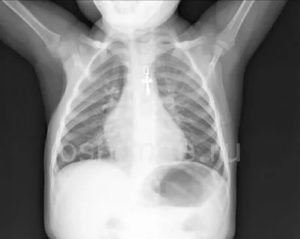

Рентгенодиагностика пневмоний у детей имеет некоторые затруднения в постановке диагноза. Обусловлено это меньшим объемом легочной ткани, большим количеством легочного рисунка, нежели у взрослого и вздутием тканей легкого. Для своевременной диагностики пневмонии важно оценивать клиническую картину заболевания.

У детей это заболевание на снимках выглядит немного иначе, чем у взрослых. Это объясняется тем, что организм ребенка реагирует на любое воспаление намного острее. Даже самый маленький инфильтрат может стать причиной крупозной формы болезни.

На рентгеновском снимке воспаление легкого у ребенка выглядит следующим образом:

- Очаги затенения локализуются в нижних отделах легких.

- Размеры инфильтратов очень маленькие. Чем выше их плотность, тем тяжелее болезнь.

- В средостении отмечается увеличение лимфатических узлов. Это отчетливо видно на рентгене.

- Участки поражения могут смазывать структуру корня легкого и полностью скрывать рисунок легочной ткани.

Из-за того, что у детей легочная ткань нередко вздувается без всякого воспаления, диагностировать пневмонию на начальных стадиях развития с помощью рентгеновских снимков бывает достаточно сложно. Кроме того, правильную диагностику при пневмонии у детей мешает поставить малый объем легочной ткани.

Пневмония у ребенка склонна к распространению и сливному характеру повреждения. Очаговая способна быстро перейти в крупозную.

Наиболее характерные признаки заболевания у ребенка:

- очаговые тени небольших размеров (не более 2 мм в диаметре);

- локализация воспаления преимущественно в нижних отделах;

- высокая плотность затемнения при прогрессировании заболевания;

- возможно уплотнение и увеличение близко расположенных лимфоузлов (средостения);

- усиление легочного сосудистого рисунка, его деформация;

- изменение структуры и размера корня легкого на стороне поражения.

После клинического выздоровления наиболее долго сохраняются изменения сосудистого рисунка и корня легкого.

Необходимо наблюдать за состоянием ребенка, направлять лечебные мероприятия на полное восстановление не только пораженной легочной ткани, а и сопутствующего локального бронхита, признаки которого сохраняются на рентгене длительное время.